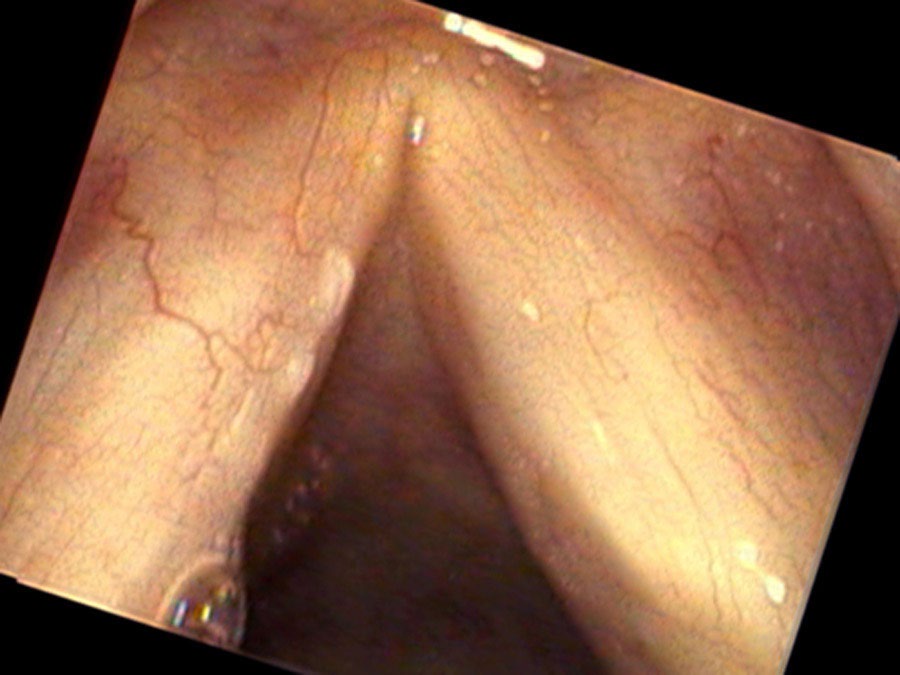

Jane Smith is in her mid-fifties. She has smoked about 10 cigarettes a day for the past 10 years. She developed a hoarse voice four months ago, though perhaps she lost some of her higher singing notes before that. She was treated with Nexium for a while and when she did not improve, she had a biopsy. The irregular area on her left vocal cord proved to be squamous cell carcinoma. When a white spot reappeared on her vocal cord shortly after the surgery removing this, she came to visit me.

We went back to surgery and re-excised the area of leukoplakia again. This time the biopsy was benign. There was no cancer, only thickening of the mucosa. Her hoarseness went away since the white spots no longer stood out from the edge of the vocal cord as much. A smaller pair of white spots came back after surgery. Rather than cut them off again, we watched the white spots with regular examinations over the next three years.

Leukoplakia may be benign or at times it may represent a cancer. After identifying abnormal white spots on the vocal cord, options for patients include treatment that removes the white patches or makes them go away, or careful observation and removing any white patches that grow over time. Cutting away part of the normal vocal cord along with leukoplakia, because it might be a cancer, might have the same cure rate, but sacrifices voice quality when a significant amount of normal tissue is removed.